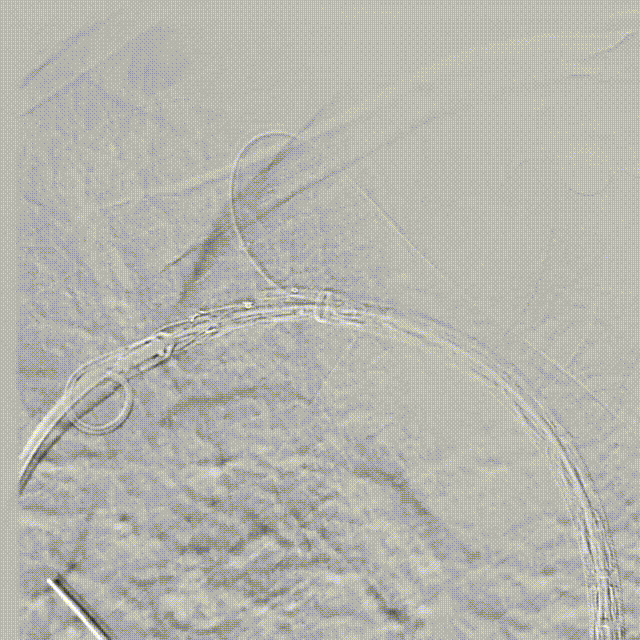

●術(shù)中(zhong)造(zao)影:

造(zao)影可(kě)見明顯潰瘍位置

沿預埋導(dao)絲(si)推送支架主(zhu)體(ti)至預期位置

支架對位準确、LSA分(fēn)支通(tong)暢

釋放分(fēn)支支架,可(kě)見病變安(an)全覆蓋(gai),支架定位準确,LSA分(fēn)支通(tong)暢,無內(nei)漏,效果滿意